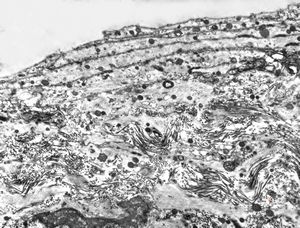

rabbit spinal cord trauma

rabbit spinal cord trauma